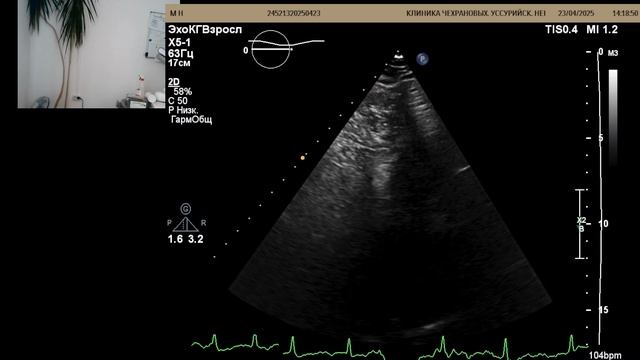

Клинические показания: ЭКС